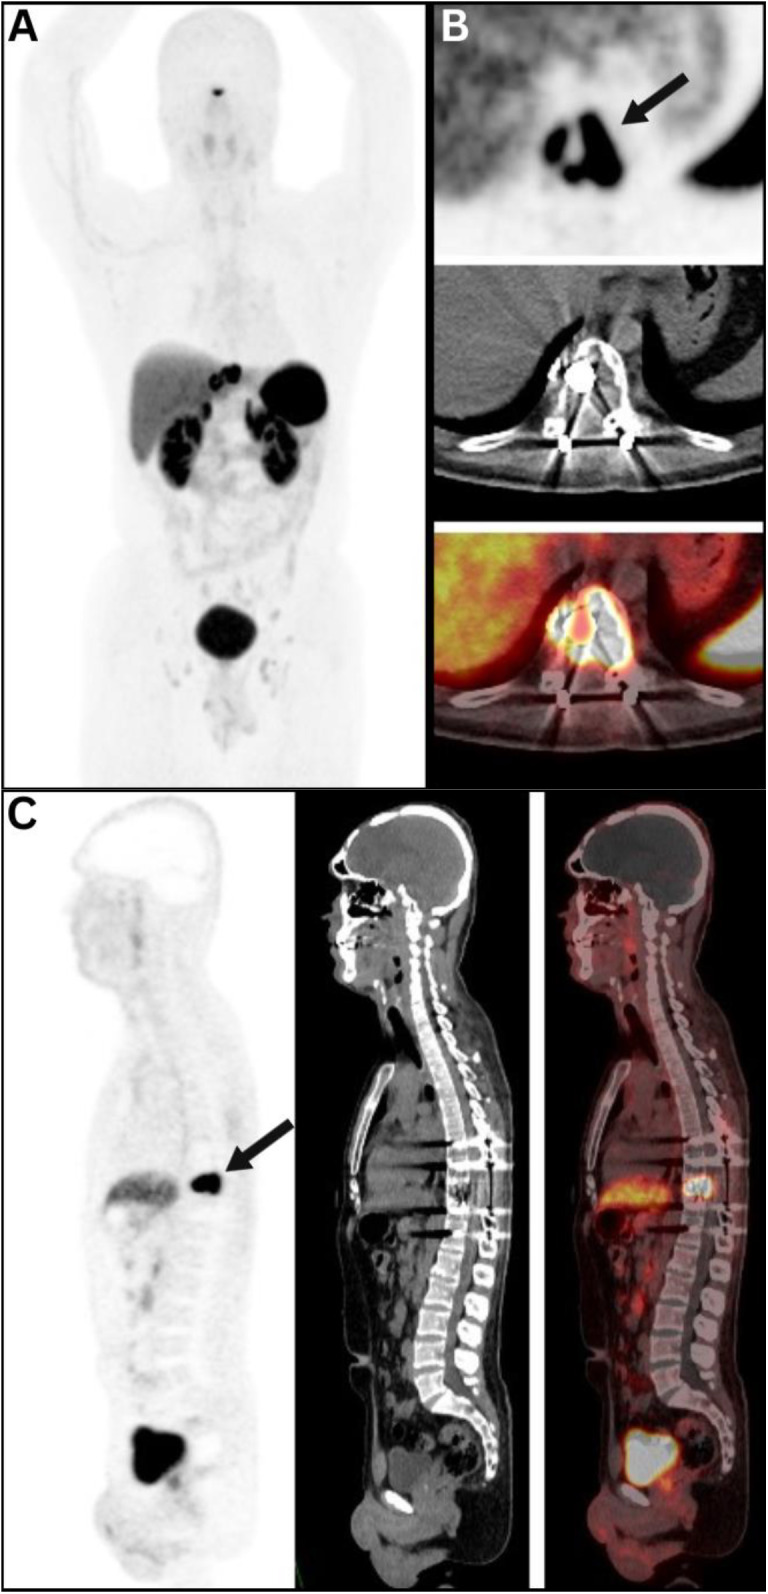

Unveiling Hemangiopericytoma: <i>A case demonstrating the utility of somatostatin receptor-positive metastatic hemangiopericytoma on <sup>68</sup>Ga-DOTA TOC PET/CT</i>.

Unveiling Hemangiopericytoma: A case demonstrating the utility of somatostatin receptor-positive metastatic hemangiopericytoma on 68Ga-DOTA TOC PET/CT.